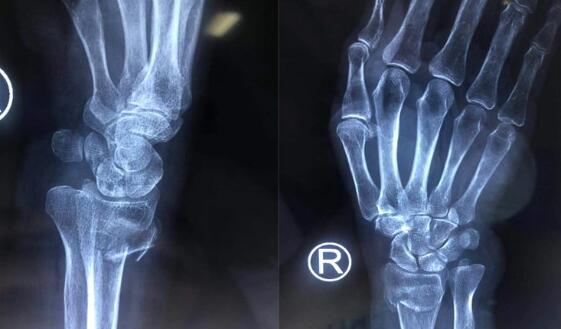

经过检查发现,老太太的右桡骨远端粉碎性骨折,骨折移位严重。手外二病区的熊祖国医师告诉王老太的家属,高龄老年患者骨质疏松,骨折愈合缓慢,选择夹板固定的保守治疗非常容易导致骨折再次移位;同时夹板固定时间长,严重影响右手、右腕功能,导致关节僵硬、活动受限,还可能会引起一些并发症,降低生活的质量。而且王老太骨折断端错位比较严重,石膏外固定已无法恢复。王老太及家人同意手术治疗。